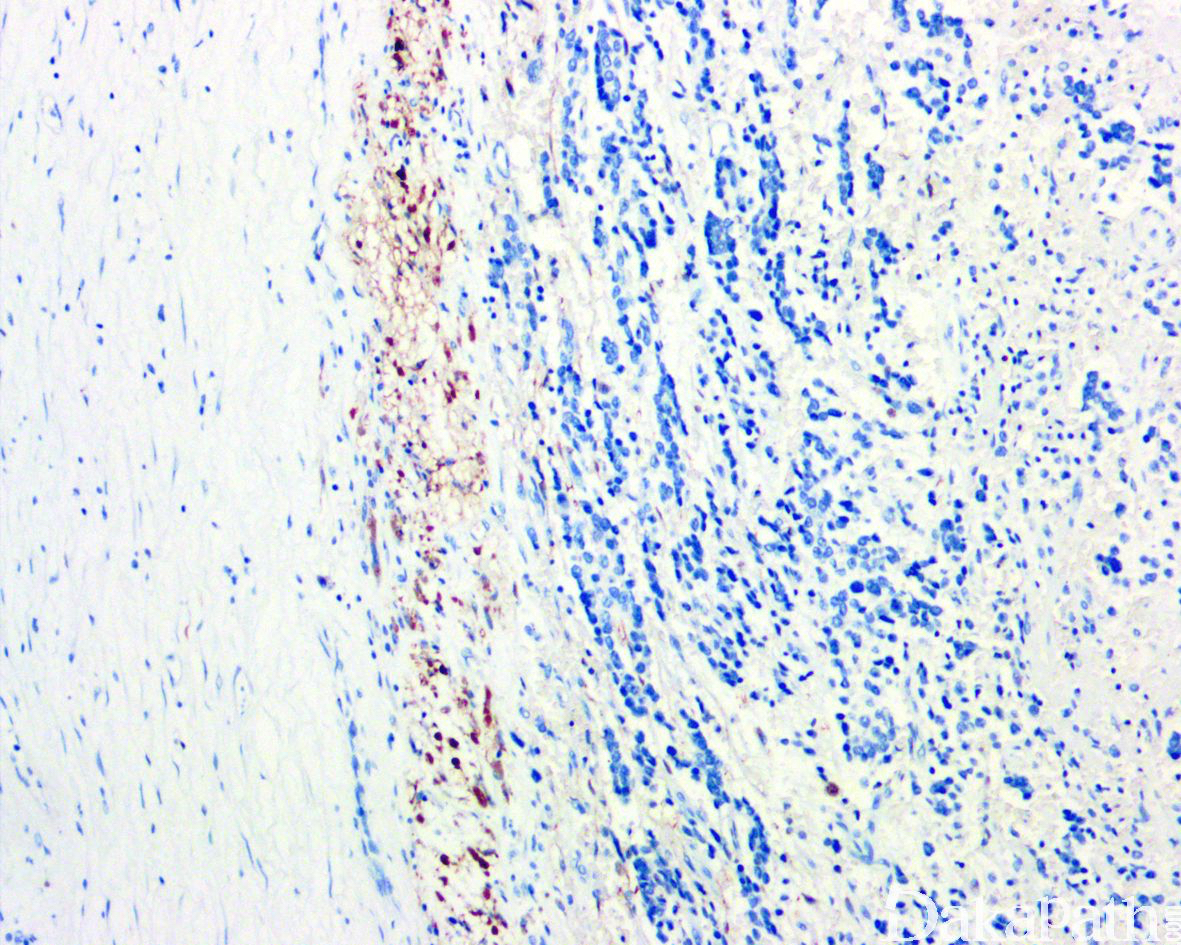

NSE 弥漫强阳性、NF、Leu-7. PHXO2B 等阳性;亦常见 synaptophysin、chromogranin、CD56 及 PGP9.5 阳性。未分化的神经母细胞弥漫表达 cyclind1 而神经节细胞不表达,GFAP、MBP、CD99 和 β-2 微球蛋白均为阴性。施万间质呈 S100 阳性。与 N-MYC 扩增相关的肿瘤可过表达 N-myc。